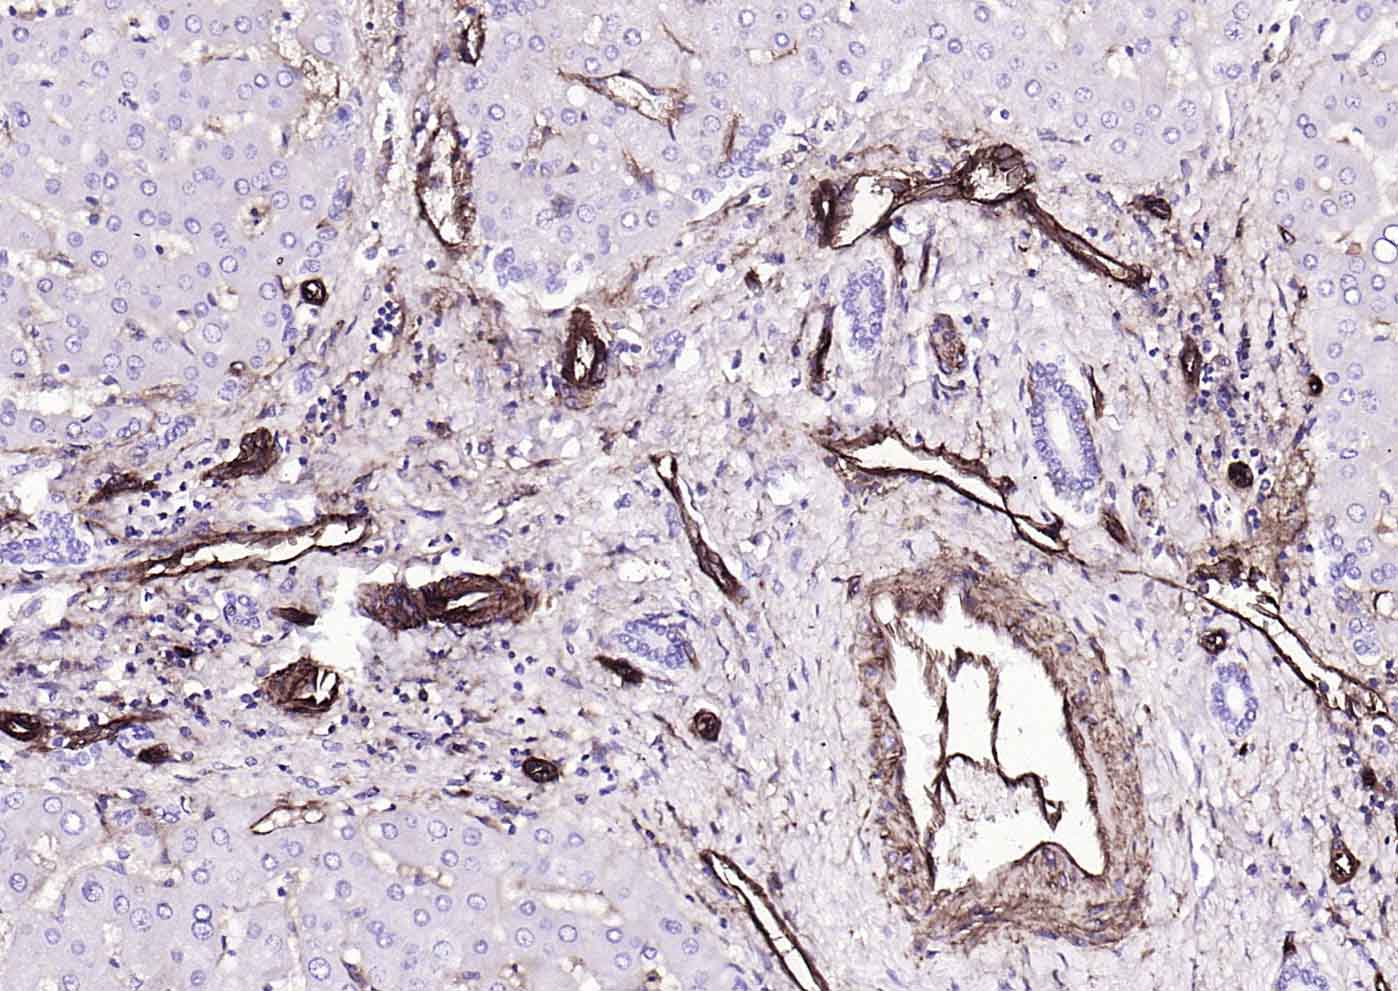

Paraformaldehyde-fixed, paraffin embedded (human liver); Antigen retrieval by boiling in sodium citrate buffer (pH6.0) for 15min; Block endogenous peroxidase by 3% hydrogen peroxide for 20 minutes; Blocking buffer (normal goat serum) at 37°C for 30min; Incubation with (CD39/ENTPD1) Monoclonal Antibody, Unconjugated (bsm-54043R) at 1:200 overnight at 4°C, followed by operating according to SP Kit(Rabbit) (sp-0023) instructionsand DAB staining.